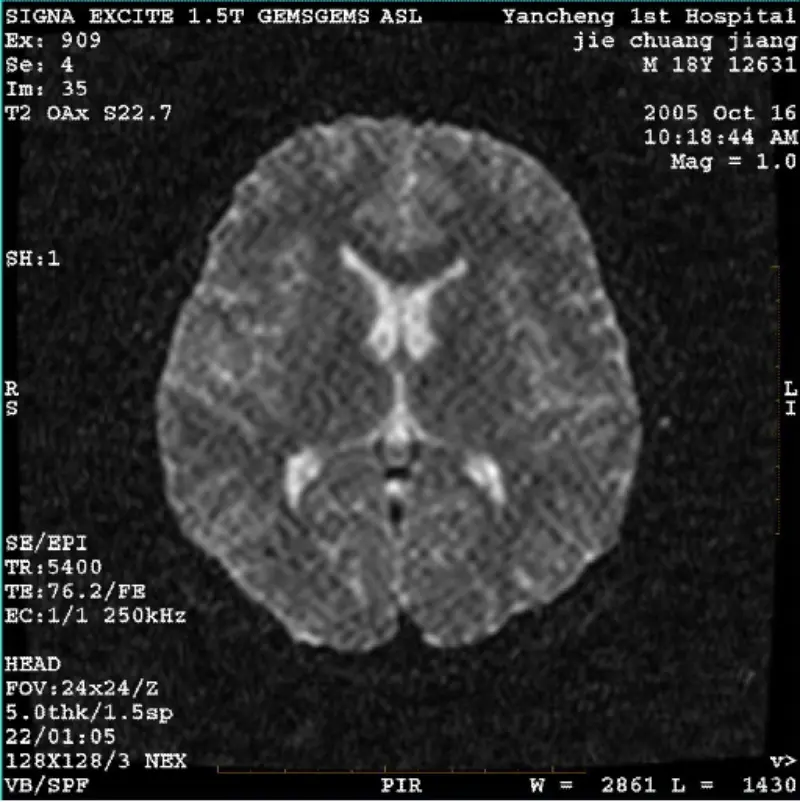

Daha çox oxuSİSTEM: 1.5T Signa Twin Excite II (Proqram Versiyası 11.0M4) PROBLEM/SIMPTO DWI (Zoom rejimi və bütün rejim) və fiesta (zoom rejimi və bütün rejim) təsvirinə malikdir gövdə rulonundan və ya başdan istifadə edildikdən asılı olmayaraq görünən retikulyar və ya korduroy artefakt coil, digər rutin......